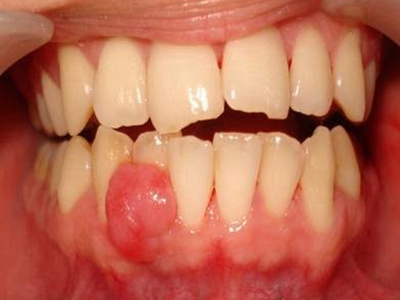

牙龈瘤是指发生在龈乳头部位的炎症反应性瘤样增生物,好发于女性,前磨牙区最为常见。牙龈瘤来源于牙周膜及牙龈的结缔组织,因其无肿瘤的生物学特征和结构,故非真性肿瘤,但切除后易复发,因此切除务必彻底,必要时拔除相关牙齿。

牙龈瘤多发于女性,以青年及中年人为常见,多发生于牙龈乳头部,位于唇、颊侧者较舌、腭侧者多,最常见的部位是前磨牙区。肿块较局限,呈圆形或椭圆形,有时呈分叶状,大小不一,直径由几毫米至数厘米。

肿块有的有蒂,如息肉状;有的无蒂,基底宽广,生长较慢,但在女性妊娠期间可能迅速增大。较大的肿块可以遮盖一部分牙及牙槽突,表面可见牙压痕,易被咬伤而发生溃疡,伴发感染。随着肿块的增长,牙槽骨壁逐渐被破坏,牙可能发生松动、移位。